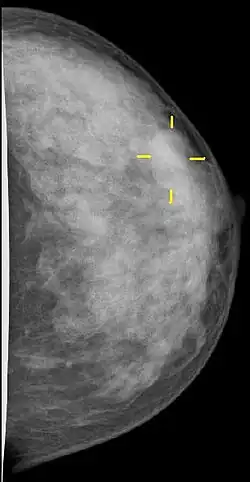

Bildgebende Verfahren

Die Röntgen-Mammographie ist einer S3-Leitlinie von 2010 zufolge zurzeit die einzige für die Erkennung von Brustkrebsvorstufen oder frühen Tumorstadien allgemein als wirksam anerkannte Methode.[91] Die Mamma-Kernspintomographie ist möglicherweise überlegen, jedoch für ein Massenscreening zu teuer.[92] In Deutschland wurde deshalb ein qualitätsgesichertes Mammographie-Screening-Programm auf der Grundlage der „Europäischen Leitlinien für die Qualitätssicherung des Mammographie-Screenings“ für Frauen von 50 bis 69 Jahren aufgebaut. Dazu wurde Deutschland in 94 Regionen aufgeteilt, für die jeweils eine Screening-Einheit verantwortlich ist.[93] 2024 wurde das Mammographie-Screening in Deutschland auf Frauen von 50 bis 74 Jahren ausgeweitet. In den USA gab es 2002 die Empfehlung, das Mammographiescreening bereits mit 40 Jahren zu beginnen.[88]

Bildgebende Diagnostik

Werden bei der Tast- oder Ultraschalluntersuchung Auffälligkeiten gefunden, folgt als nächste Untersuchung üblicherweise die Mammographie: Die Röntgenaufnahmen werden aus zwei Blickrichtungen (von der Seite und von oben) gemacht, bestimmte Veränderungen erfordern manchmal zusätzliche Aufnahmen. Die Galaktographie wird nur durchgeführt, wenn die Brustwarzen Sekret absondern. Als Ergänzung steht bei einer solchen Sekretion an einigen Zentren die Duktoskopie, eine Spiegelung der Milchgänge, zur Verfügung.

Umgekehrt werden mit der Mammographie entdeckte Veränderungen immer sonographisch weiter untersucht. Dabei werden gutartige Zysten erkannt. Die Kassenärztliche Bundesvereinigung schrieb 2003 hierfür Schallköpfe mit mindestens 5 MHz Frequenz vor.[101] Mittlerweile ist dieser Wert auf 7,5 MHz erhöht worden.[102]

Die Kernspintomographie der Brust (MR-Mammographie, MRT) wird zurzeit nur empfohlen für das invasive lobuläre Mammakarzinom zur Bestimmung der Resektions-Grenzen und allgemein bei Verdacht auf das Vorliegen mehrerer Tumorherde,[103] gegebenenfalls ist auch eine MRT-gesteuerte Biopsie möglich. Nach brusterhaltender Therapie kann die MRT eingesetzt werden, um zwischen narbigen Verdichtungen in der operierten Brust und neuem Tumorwachstum zu unterscheiden. Außerhalb der ambulanten Versorgung der gesetzlich krankenversicherten Patientinnen gibt es weitere Indikationen.

Gewebeentnahmen

Wurde mit dem Ultraschall und der Mammographie ein Tumor diagnostiziert, wird dieser auf seine Gut- oder Bösartigkeit untersucht. Dazu werden jedem Tumor mittels Stanzbiopsie, in seltenen Fällen mittels Vakuumbiopsie, mehrere Gewebeproben entnommen und unter dem Mikroskop auf Krebszellen untersucht. Methode der Wahl für die Probenentnahme tastbarer und sonografisch sichtbarer Befunde ist die Stanzbiopsie, für im Kernspintomogramm sichtbare Befunde und Mikrokalzifikationen die stereotaktisch gestützte Vakuumbiopsie. Wurde der Tumor als bösartig erkannt, wird das Karzinom durch weitere Untersuchungen des entnommenen Gewebes näher bestimmt. Hierzu gehören der Status der Hormon- und HER2/neu-Rezeptoren sowie der Entartungsgrad.